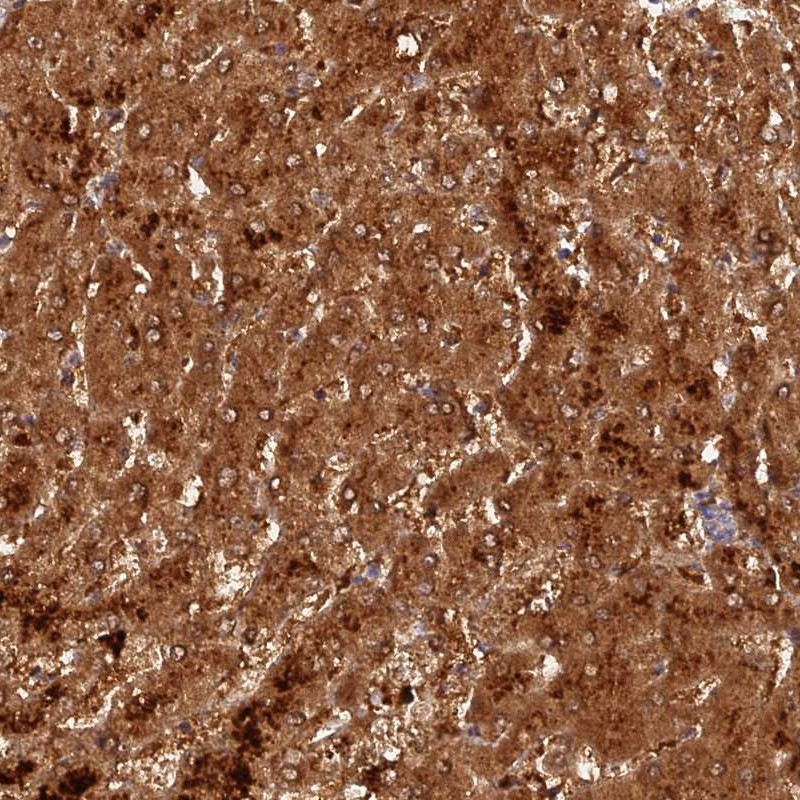

Immunohistochemical staining of human liver shows strong cytoplasmic positivity in hepatocytes.